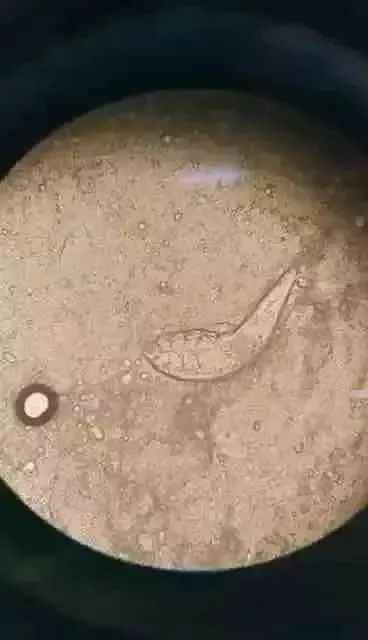

医生通过显微镜等检查大吃一惊,发现徐婆婆双眼睫毛内寄生了大量螨虫,有的单个毛囊里甚至“蜗居”着数十只,粗略估算螨虫总数量达百余只!